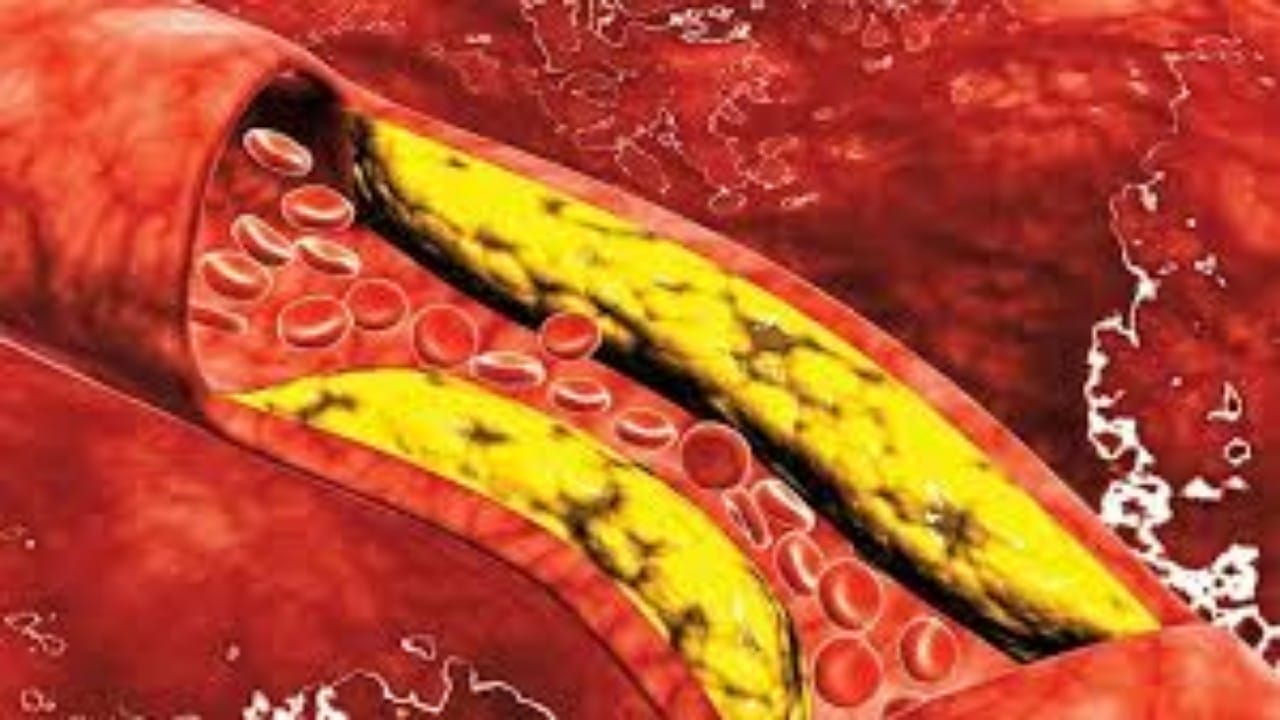

مشكلات في الساقين تنذر بارتفاع مستوى الكوليسترول في الدم